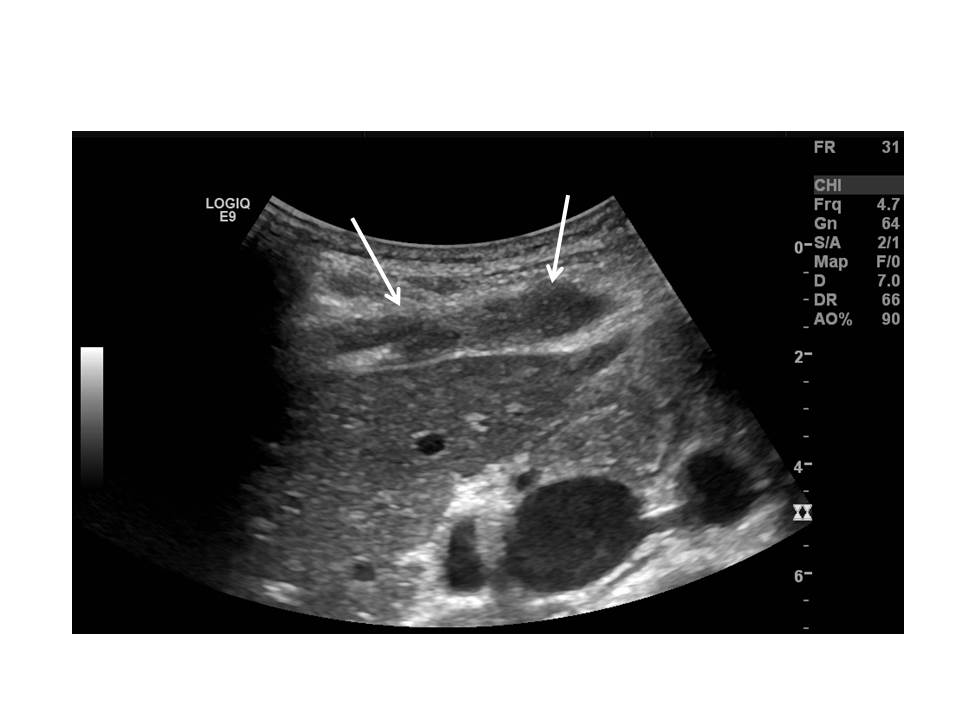

A 37 year-old lady with a three month history of pain in the right upper quadrant was referred by her GP for an abdominal ultrasound. She also had a long history of pelvic pain.

Ultrasound images are shown in Figs 1, 2 and 3.